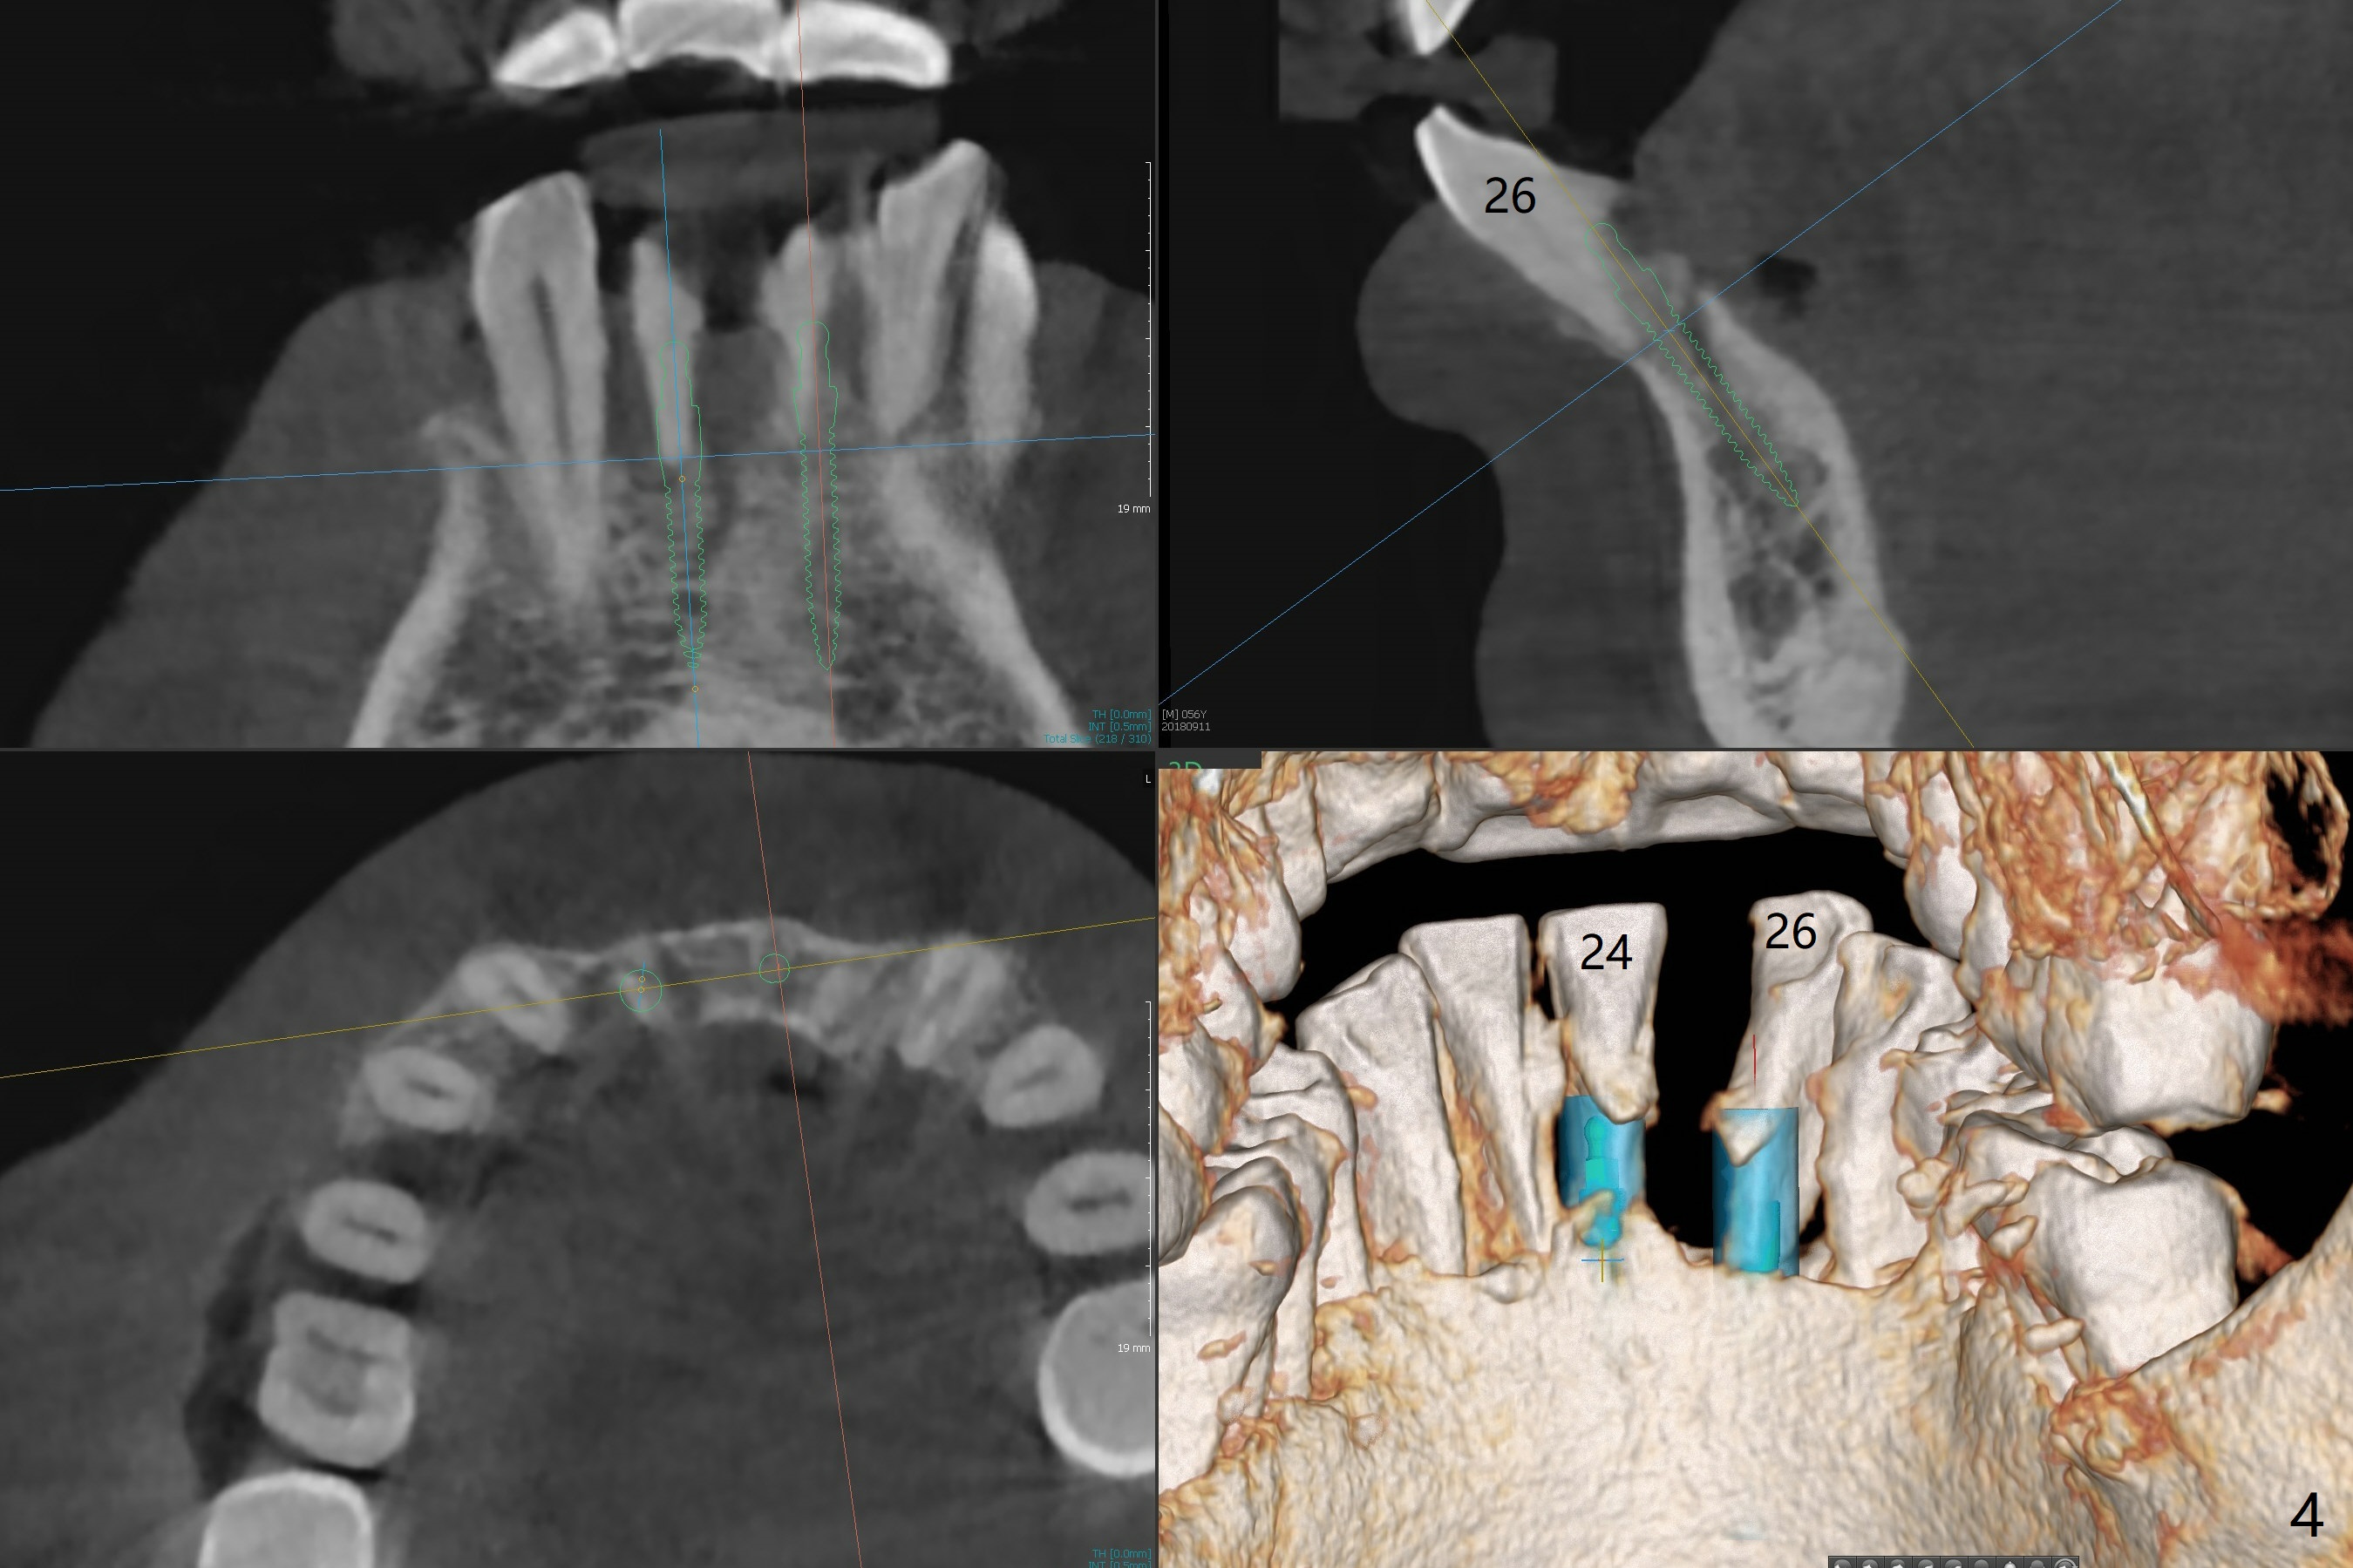

A 56-year-old man is a dental phobic. He finally seeks treatment because of loss of the tooth #25 with air leakage during speech (Fig.1). If the remaining lower incisors are stable after scaling and root planing, a 2.5 or 2.0 mm 1-piece implant will be placed in the narrow edentulous space (Fig.2). The implant driver (green sleeve) may touch the neighboring teeth, which need adjustment. If the worst incisor (#26 tender prior to SRP) is deemed to be non-salvageable, a 2.5 mm implant will be placed with a cantilever 2-unit FPD (Fig.3). If the tooth #23 is a survivor, two of 2.5 or 2.0 implants will be placed at #24 and 26 with a subsequent FPD (Fig.4). If the remaining incisors are all questionable in prognosis, two implants will be placed in the ends with a FPD (Fig.5). After SRP, the tooth #26 is less tender; the patient is ok with its extraction, but insists on saving #23 and 24. If 2 implants are to be placed at #25 and 26, they need to be 2 mm in diameter (Fig.6) with risks of injuring the neighboring teeth. It appears that it is more reasonable to have a single implant, slightly larger (2.5 or 3 mm), at #26, with the coronal end slightly mesial (Fig.7) with a cantilever bridge. If the teeth #23 and 24 fail in the future, a normal one will be easily converted.